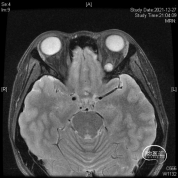

头颅MR体检偶然发现左侧眶尖占位,初步诊断海绵状血管瘤,查体无明显阳性体征。

磨除局部少许隆起的骨嵴以增加操作空间,切开眶骨膜分离并完整切除病变,术中证实为海绵状血管瘤,直径约1厘米,手术全程在内镜下完成。

患者术后除眼睑稍肿胀,视力视野及眼球运动一切正常!